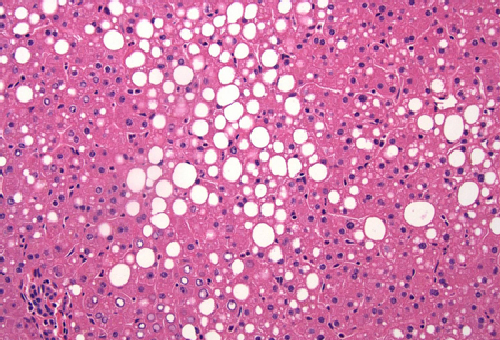

JNK and metabolism

JNK promotes hepatic steatosis by suppressing the activity of the PPARa nuclear hormone receptor.